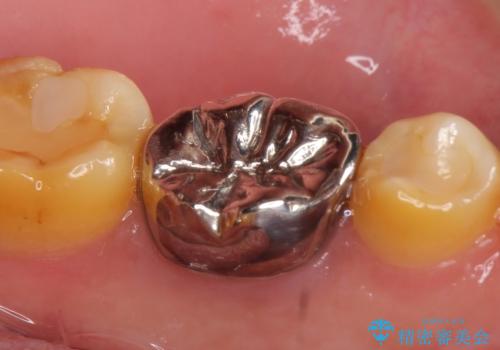

咬合痛等の症状の緩解、根尖病変の縮小傾向、および深かったポケットが正常値まで改善したことを確認後、オールセラミッククラウンによる補綴を行いました。

オールセラミッククラウンの色に関しては、患者様の希望により他歯より白い色で製作しました。

今回用いたオールセラミッククラウンはジルコニアフレームという白い素材の上にセラミックを盛っているため、審美性が非常に高いのが特徴です。

また、ジルコニアは人工ダイヤモンドの材料にも使われているほど高い強度を持っており、そのためオールセラミッククラウンは審美性だけでなく、奥歯やブリッジの補綴も可能とするクラウンです。